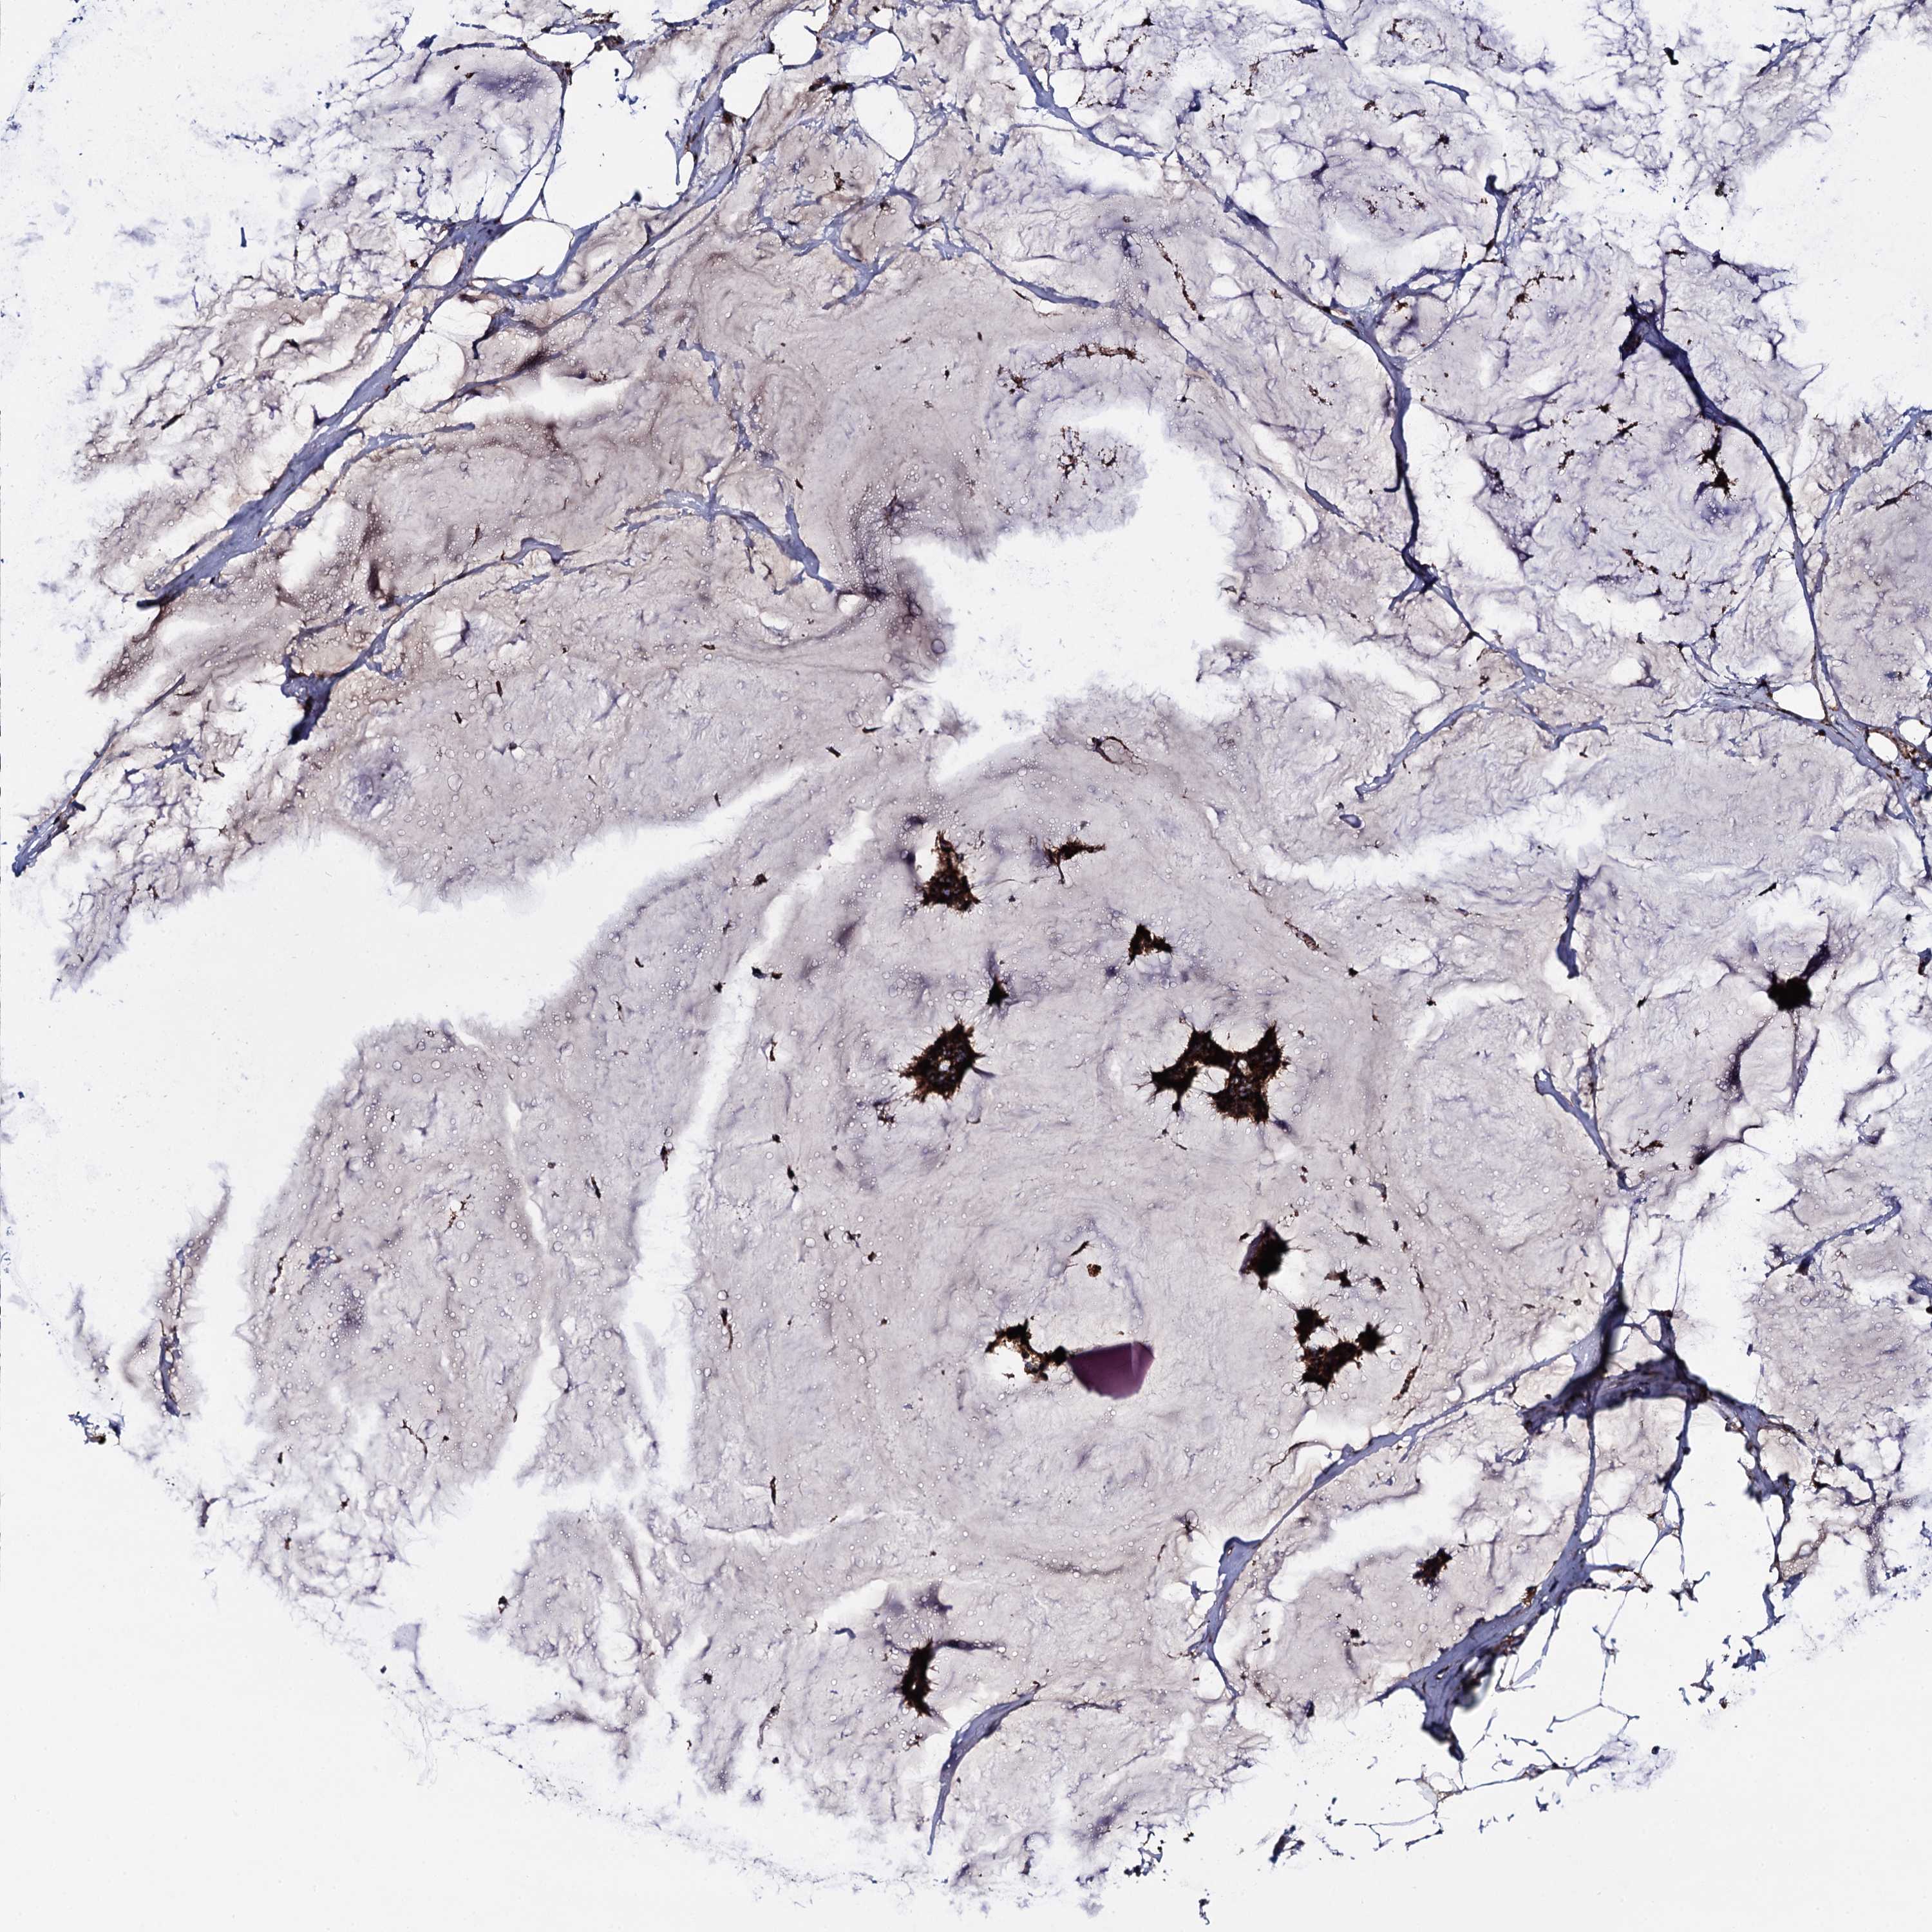

CANCER BREAST CANCER Show tissue menu

BRCA TCGA BRCA VALIDATION PROTEIN EXPRESSION

ANTIBODIES

AND

VALIDATION